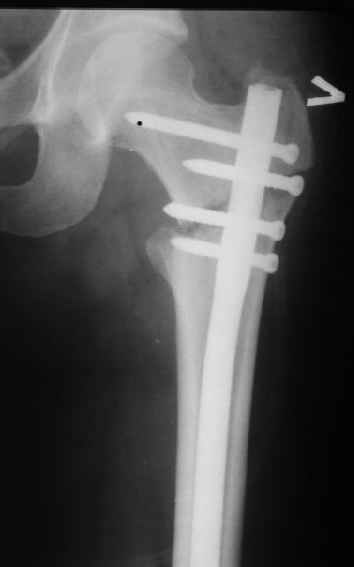

Женя, эта картинка показывает не оптимальное лечение вертельных переломов в моем представлении, а особенности дизайна упомяутого фиксатора.

В частности, его возможности при фиксации переломов проксимального отдела бедра - в сравнении с другими, имеюшими лишь по одному статическому и динамическому отверстию и с кондуктором для введения 2 винтов.

Это было года 2,5 назад, мы тогда еще уточняли возможности шинирования с угловой стабильностью гвоздем с поперечным расположением винтов при переломах проксимального отдела бедра. Пациенту не пришлось приобретать намного более дорогой рекон или проксимальный гвоздь. В приложении еще несколько примеров применения того гвоздя при высоких переломах бедра, в том числе с более латеральной точкой входа. Гвоздь изгибаем для этого.